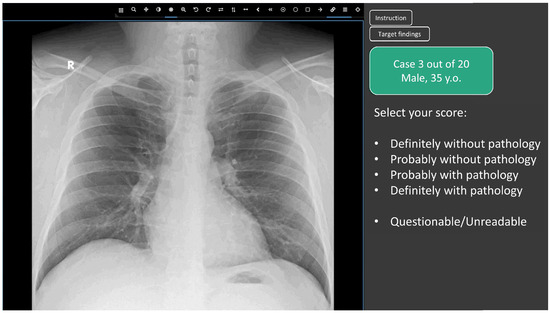

2.3. Web Platform for Conducting the Reader Study

- Definitely without pathology (probability of pathology = 0.0);

- Probably without pathology (probability of pathology = 0.25);

- Undefined (questionable/unreadable) (probability of pathology = 0.5)

- Probably with pathology (probability of pathology = 0.75);

- Definitely with pathology (probability of pathology = 1.0);